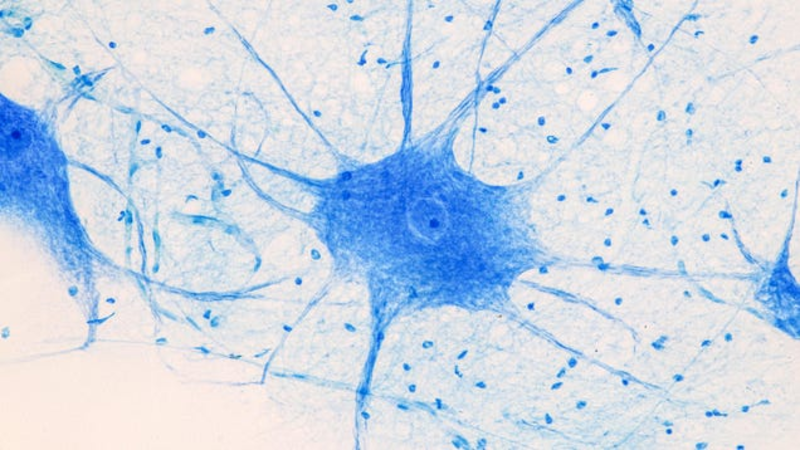

New research links the rare neurological condition Guillain-Barré syndrome to covid-19. The study tracked millions of people in Israel, finding that those with a recent history of covid-19 infection were noticeably more likely to develop Guillain-Barré than those without one. Conversely, covid-19 vaccination appeared…